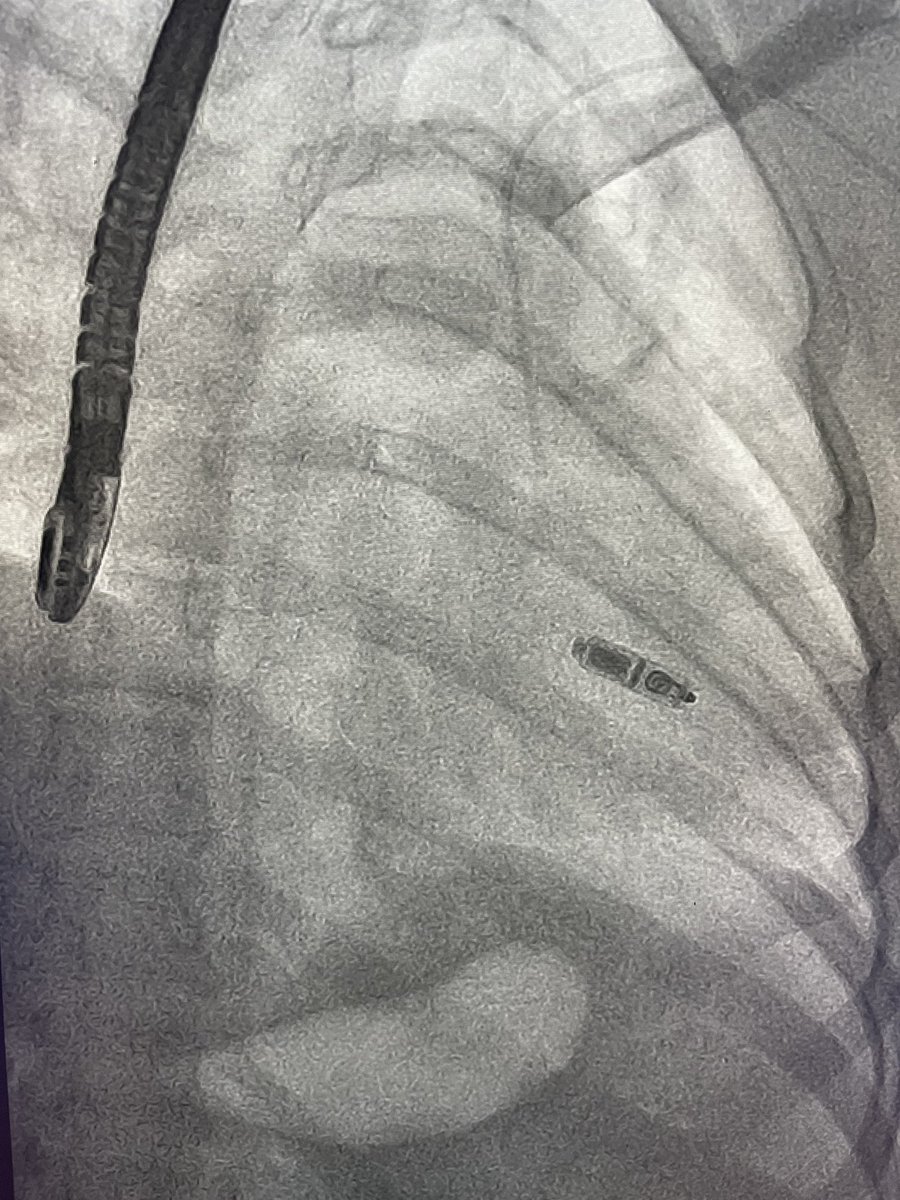

Third Micra @MDT_Cardiac at Las Higueras Hospital, Chile. The program continues growing. @FellowEP @ABeaser @gauravaupadhyay @DrRoderickTung @LAHRSonline1

Second Micra implant at Las Higueras Hospital, Chile. Our program continues growing. @ABeaser @HNayakEP @DrRoderickTung @gauravaupadhyay @FellowEP @MDT_Cardiac

First Micra AV implant at Hospital las Higueras, Chile!!!… excellent result, thanks to the @MDT_Cardiac team support….@HNayakEP @ABeaser @DrRoderickTung @FellowEP @gauravaupadhyay